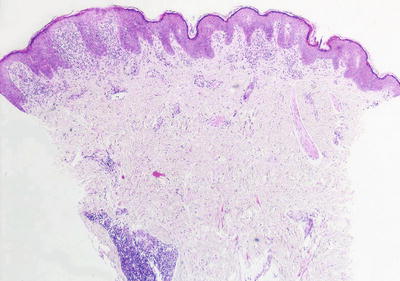

Lichen planus occurring in children has similar histologic features to the same disease in adults. The stratum corneum is hyperkeratotic without acanthosis. The epidermis is acanthotic with hypergranulosis (Fig. 4.2). The rete ridges demonstrate a saw-toothed alteration in appearance. The basal layer is disrupted and in some places obscured by a dense, band-like infiltrate of lymphocytes along the dermal epidermal junction (Fig. 4.3). Dying keratinocytes are present either focally or extensively, resulting in separation of the epidermis from the dermis. In some cases, this may present with clinically apparent bullae (bullous lichen planus) [2]. In older lesions, especially in patients with darker skin tones, post-inflammatory pigment incontinence is detected in the presence of papillary dermal melanophages (lichen planus pigmentosus in its most extensive form). The inflammatory infiltrate consists of lymphocytes and histiocytes. Eosinophils and plasma cells are not common. The infiltrate is restricted to the papillary dermis, and does not ordinarily extend into the reticular dermis [3–5].

Fig. 4.2

Lichen planus has orthokeratotic hyperkeratosis, hypergranulosis, acanthosis and a bandlike lymphocytic infiltrate in the papillary dermis